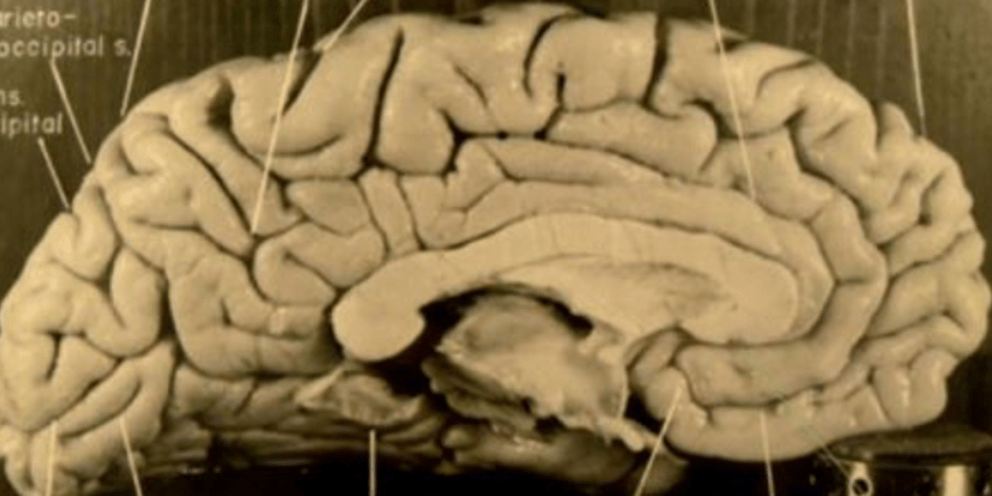

Σχεδόν αμέσως μετά την τελευταία του πνοή το 1955, ο εγκέφαλος του διάσημου φυσικού αφαιρέθηκε από το κρανίο του, κόπηκε και κομμάτια και φωτογραφήθηκε προκειμένου να μελετηθεί από τον παθολόγο Τόμας Χάρβεϊ, ο οποίος διενήργησε την αυτοψία.

Στο πλαίσιο λοιπόν νέας μελέτης, ερευνητές από το East China Normal University στην Σαγκάη και το Florida State University μελέτησαν λεπτομερειακά 14 πρόσφατα ευρεθείσες φωτογραφίες του εγκεφάλου του Αϊνστάιν και συνέκριναν τις δέσμες ινών που συνδέουν το δεξί με το αριστερό ημισφαίριο με εκείνες κανονικών καθημερινών ατόμων ηλικίας 70-70 ετών, δεδομένου ότι όταν πέθανε, ο μεγάλος φυσικός βρισκόταν στο 76ο έτος του.

Αυτό που βρήκαν ήταν ότι οι δέσμες ινών του εγκεφάλου του ήταν σε πολλές υπο-περιοχές πιο παχιές, πράγμα που υποδεικνύει καλύτερη συνδεσιμότητα μεταξύ των μερών του εγκεφάλου σε σχέση με τους περισσότερους ανθρώπους.

Και παρ' όλο που η ευφυΐα ενός ανθρώπου δεν μπορεί να εξηγηθεί πλήρως από μία τέτοια μεμονωμένη διαπίστωση, ωστόσο τα ευρήματα υποδεικνύουν ότι οι εξαιρετικές γνωσιακές ικανότητες του Άινσταϊν σε μεγάλο βαθμό οφείλονταν στις περισσότερο εξελιγμένες επικοινωνιακές οδούς ανάμεσα σε μερικά τουλάχιστον μέρη των δύο ημισφαρίων του εγκεφάλου του.

Ωστόσο, η ποιότητα των φωτογραφιών δεν επιτρέπει την περαιτέρω εξαγωγή ασφαλών συμπερασμάτων.